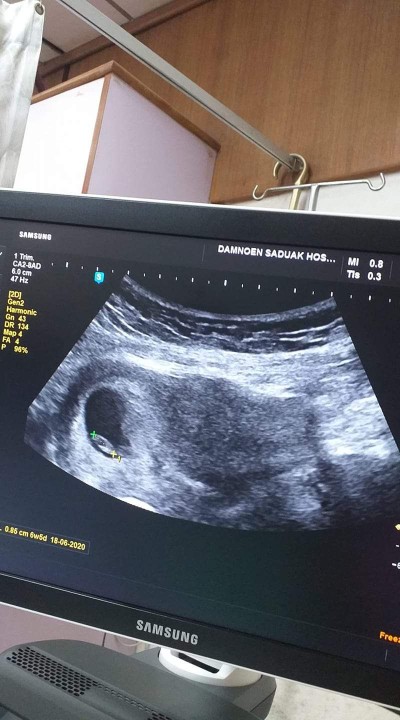

ตอน 6w 3d